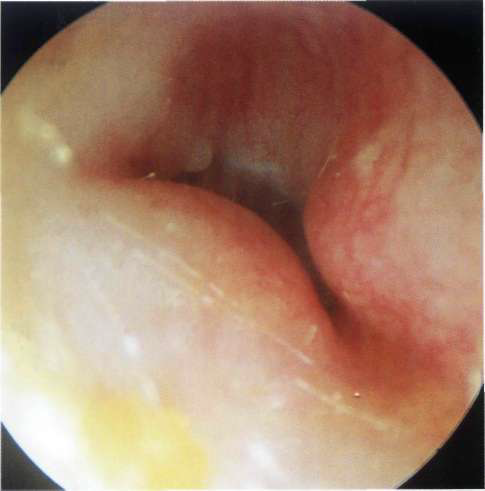

Oido Izquierdo normal

Oido izquierdo Una membrana timpánica normal que es ligeramente adelgazada en el cuadrante anterior y moderadamente engrosada en el posteriorExóstosis y osteoma